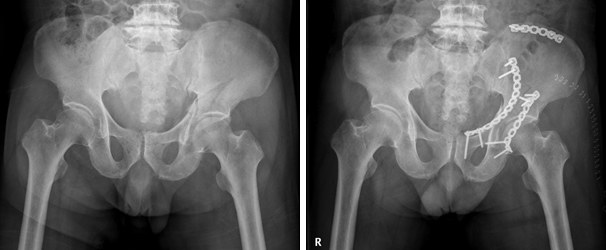

비구 골절과 천골 골절의 외고정술 비구 골절과 천골 골절의 외고정술 이미지